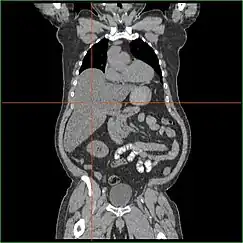

Hepatomegaly via CT scan.

Hepatomegaly with enlarged liver visible in red crosshairs and extending downward.

Impairment in the liver's ability to perform gluconeogenesis leads to clinically apparent hepatomegaly. Without this process, the body is unable to liberate glycogen from the liver and convert it into blood glucose, leading to an accumulation of stored glycogen in the liver. Hepatomegaly from the accumulation of stored glycogen in the liver is considered a form of non-alcoholic fatty liver disease. GSD I patients present with a degree of hepatomegaly throughout life, but severity often relates to the consumption of excess dietary carbohydrate. Reductions in the mass of the liver are possible, since most patients retain residual hepatic function that allows for the liberation of stored glycogen at a limited rate.

GSD I patients often present with hepatomegaly from the time of birth. In fetal development, maternal glucose transferred to the fetus prevents hypoglycemia, but the storage of glucose as glycogen in the liver leads to hepatomegaly. There is no evidence that this hepatomegaly presents any risk to proper fetal development.

Hepatomegaly in GSD type I generally occurs without sympathetic enlargement of the spleen. GSD Ib patients may present with splenomegaly, but this is connected to the use of filgrastim to treat neutropenia in this subtype, not comorbid hepatomegaly. Hepatomegaly will persist to some degree throughout life, often causing the abdomen to protrude, and in severe cases may be palpable at or below the navel. In GSD-related non-alcoholic fatty liver disease, hepatic function is usually spared, with liver enzymes and bilirubin remaining within the normal range. However, liver function may be affected by other hepatic complications in adulthood, including the development of hepatic adenomas.